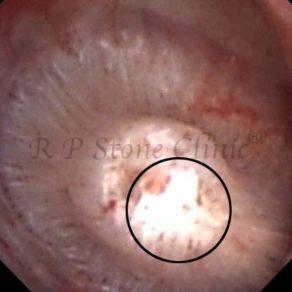

These images are taken as snap shots from the video recording of RIRS Surgery done at our hospital. These are Randall’s Plaques seen with Digital FLEX XC & Digital FLEX XC S. The cream or whitish patches are seen on the tips of RENAL PAPILLAE as seen in images below.

The Below Images Show Small Stones attached to the Renal Papillae.